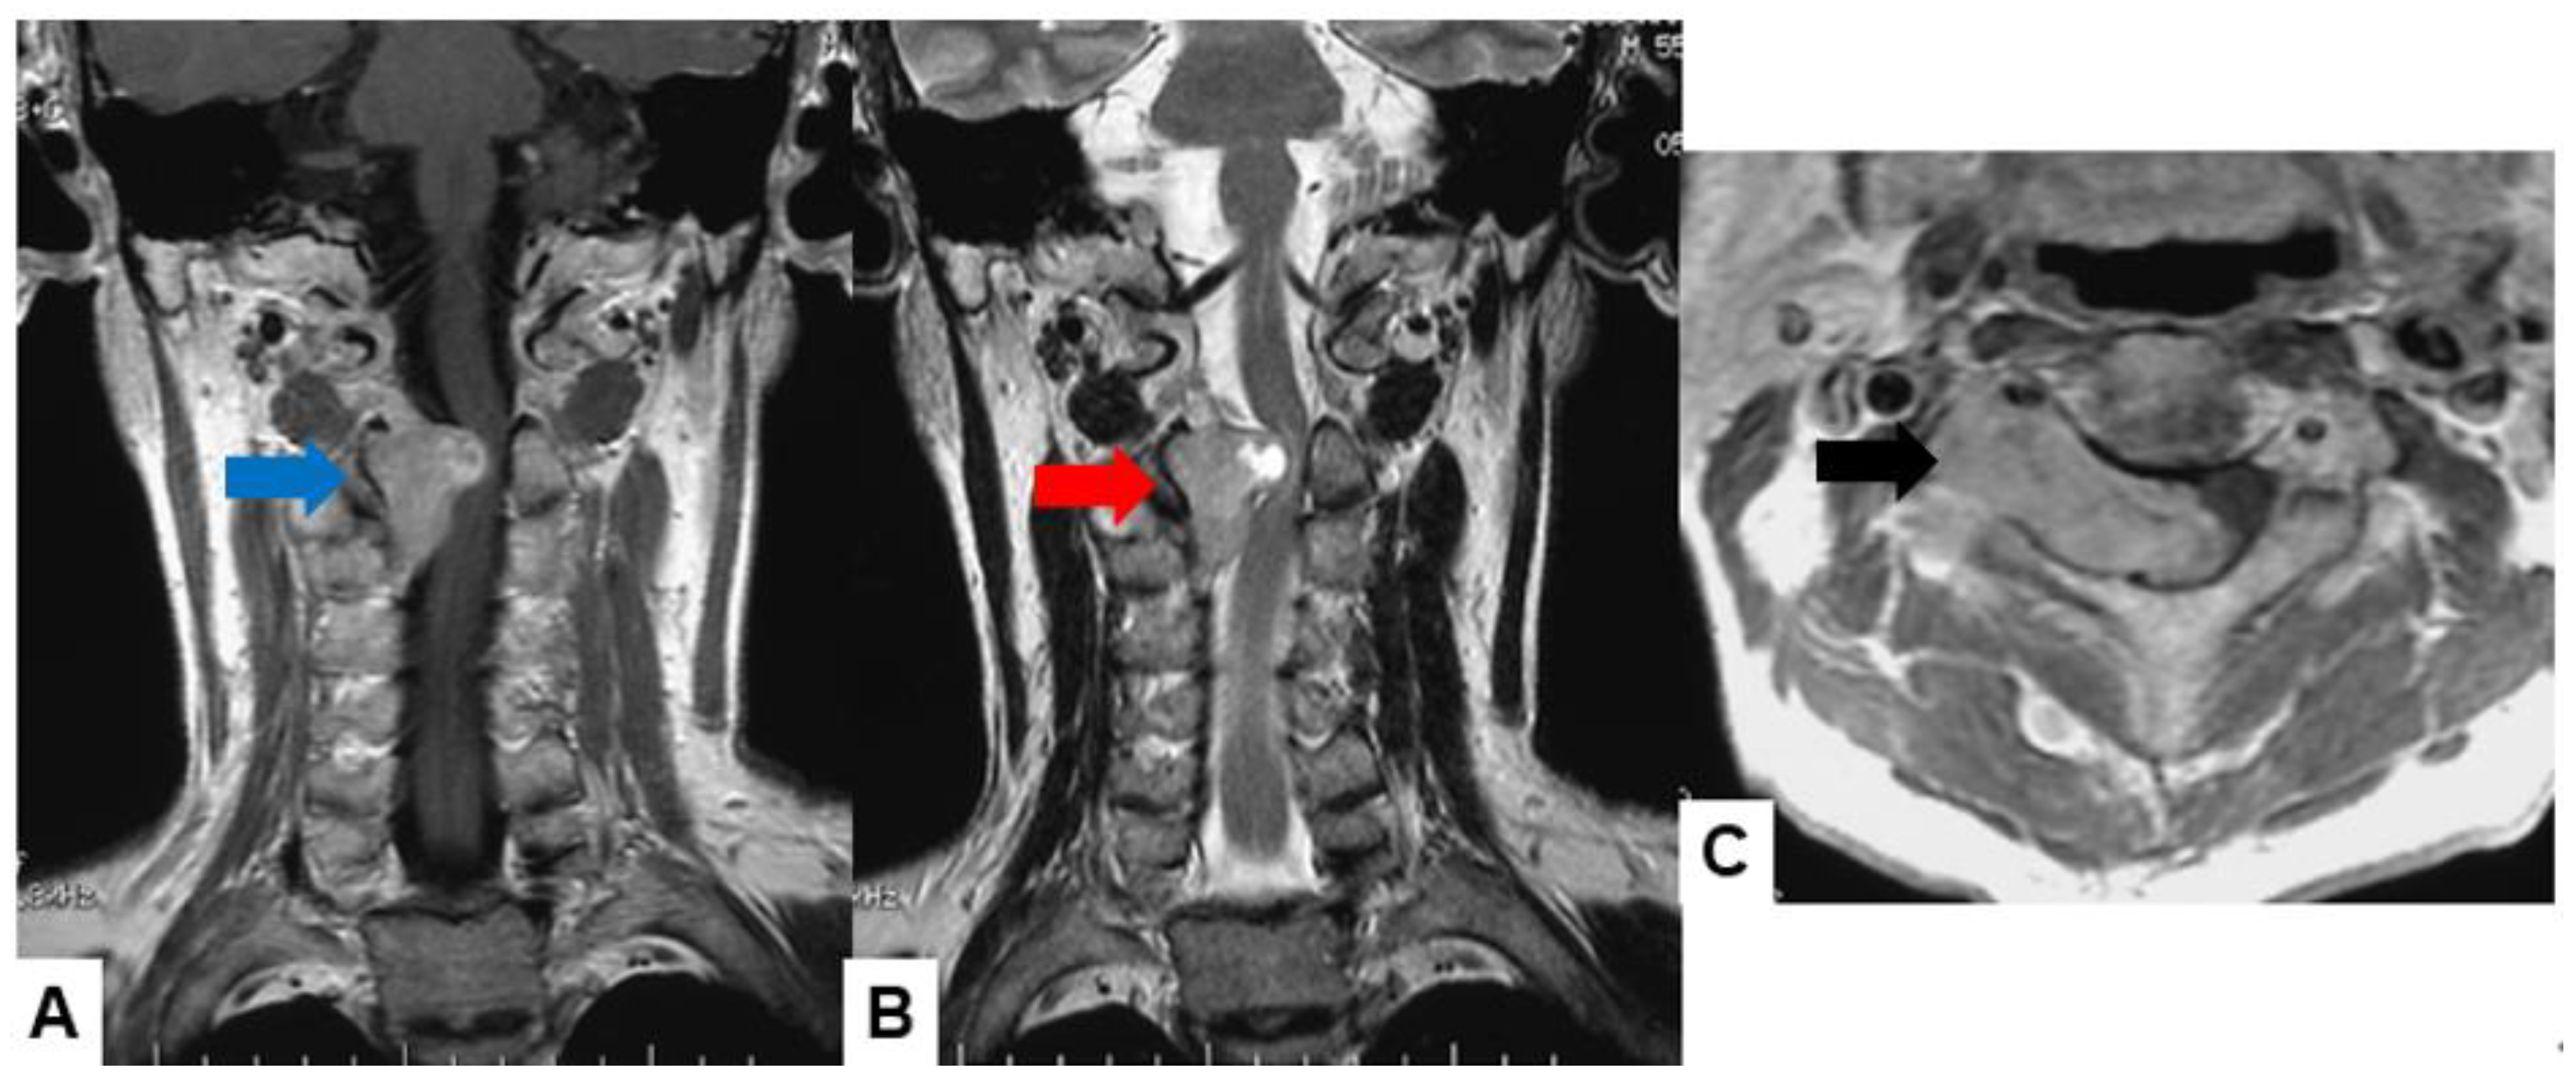

Schwannomas usually show low intensity in T1-weighted MR imaging and high intensity in T2-weighted MR imaging (Figure 1 and Figure 2). These tumors often enlarge alongside the nerve root and become a dumbbell-type [34]. The heterogenicity of a tumor indicates cystic change.

Figure 2.

Fifty-five M, spinal schwannoma. (A) Enhanced T1-weighted midsagittal image, (B) T2-weighted midsagittal image, and (C) enhanced T1-weighted axial image at C2/3. Red arrow indicates tumor and blue arrow shows tumor enhancement. The tumor is dumbbell-shaped (black arrow).